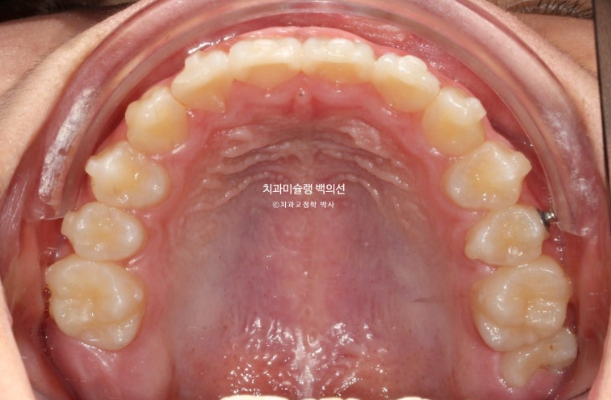

24년 2월부터 9월까지 첫세트의 19개 장치를 모두 낀 후 모습입니다.

24.09

중심선은 개선되었으나 약간의 불일치가 남아있으며 반대교합과 덧니는 모두 개선되었습니다.

그 사이 하나 남아있던 유치가 빠지고 완전한 영구치열에 접어들었습니다.

중심선 개선을 위해 추가장치 제작을 하기로 합니다.